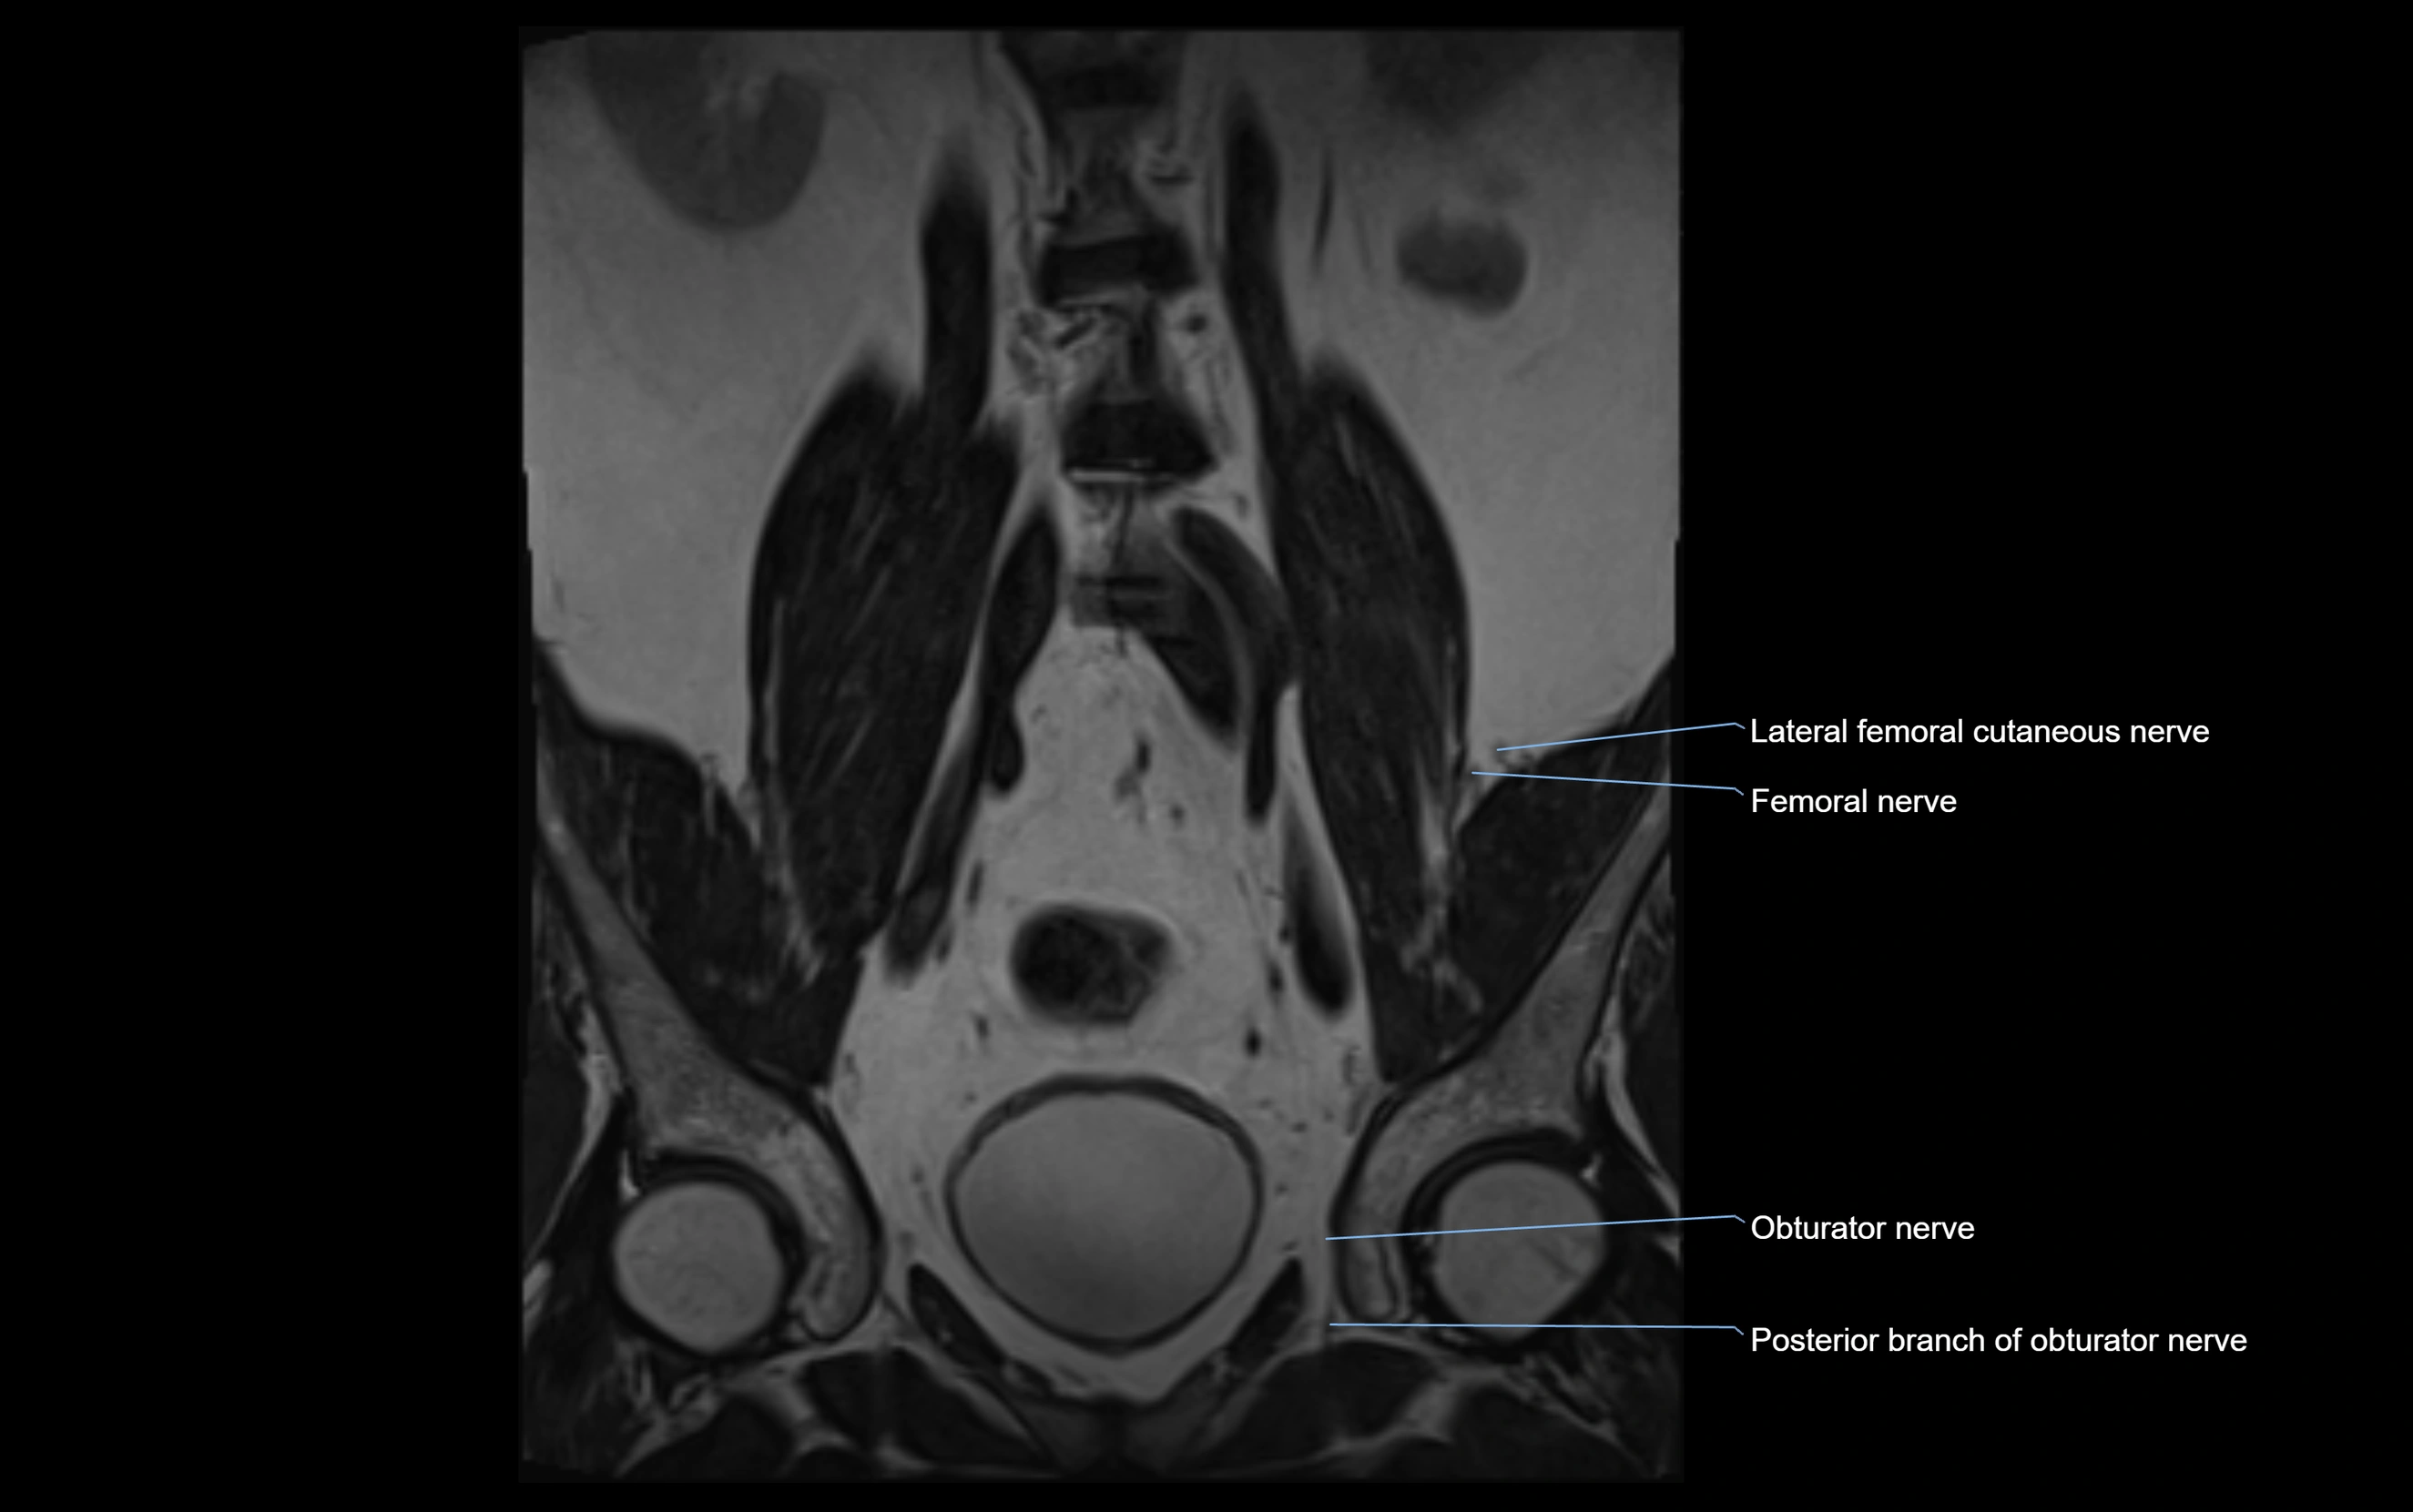

MRI Appearance

T1-weighted images:

• Nerve appears as a very thin low-to-intermediate signal intensity structure

• Surrounded by bright fat, aiding visualization

T2-weighted images:

• Nerve shows intermediate to mildly hyperintense signal compared to muscle

• Pathological involvement appears brighter

STIR (Short Tau Inversion Recovery):

• Normal nerve appears dark

• Inflamed or entrapped nerve appears bright hyperintense

T1 Fat-Sat Post-Contrast:

• Normal nerve enhances minimally

• Pathologic nerve (neuritis, entrapment, tumor infiltration) shows focal or diffuse enhancement

3D T2 SPACE / CISS:

• Nerve appears intermediate to mildly hyperintense compared to muscle

• Surrounded by bright fat or CSF, improving visualization

• Best sequence for mapping small pelvic nerves such as the anococcygeal

MRI image

image